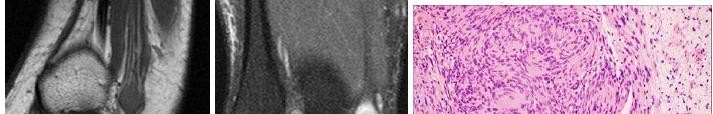

A 15-year-old male presents with deep knee pain awakening him at night. Radiographs show a permeative destructive lesion in the distal femoral metaphysis with a 'sunburst' periosteal reaction and Codman's triangle.

Biopsy confirms high-grade conventional osteosarcoma. What is the most critical prognostic factor for long-term overall survival in this patient?

Explanation

For localized high-grade osteosarcoma, the most important prognostic indicator is the histologic response to neoadjuvant chemotherapy. This is evaluated during the definitive resection. A 'good response' is typically defined as greater than 90% or 99% tumor necrosis. Patients who achieve this level of necrosis have a significantly improved disease-free and overall survival rate compared to 'poor responders' who have extensive viable tumor cells remaining.